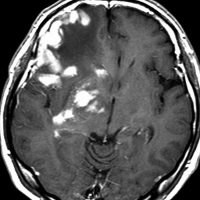

若い患者さんのリンパ腫です。左が診断時MRIで,黄色の矢印でみれる3ヶ所に同時にリンパ腫が発生しています。定位生検術後にすぐにMTX化学療法を3コースしたら,真ん中の画像になりました。ほとんど消失しているのですが,矢印の先にぼーっと少し残っているのでCR(消失)とはいいません。化学療法を終えた後に全脳照射30グレイをしたら右の画像になり治りました。これは順調な治療経過の例です。